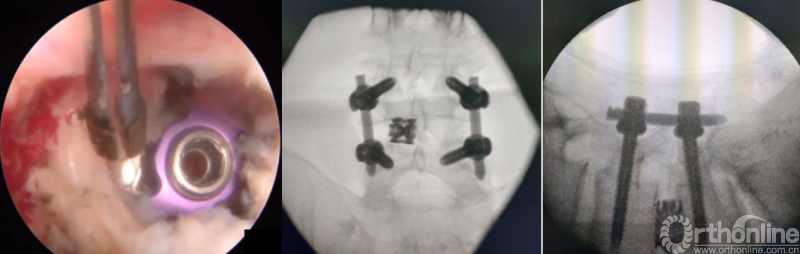

第八步“铰”:盲视下可撑开铰刀置入,撑开并处理上下终板;

第九步“填”;椎间隙填塞植骨;

第十步“置”:置入融合器、经皮钉。